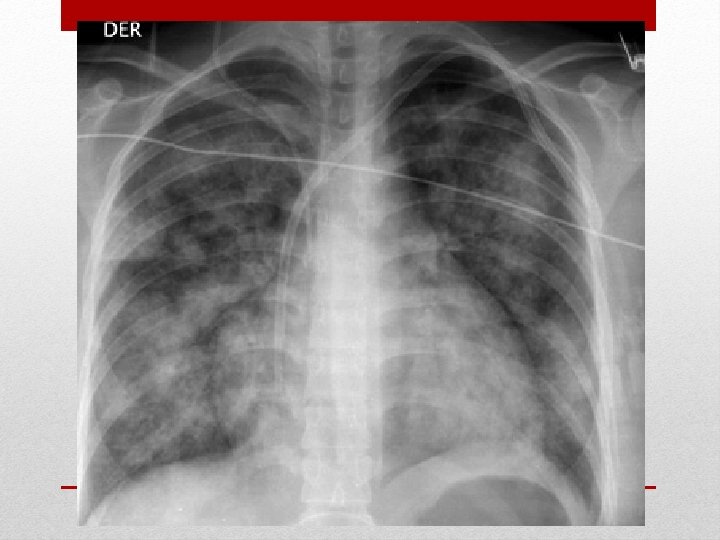

Radiografía de Tórax

• Síntomas: disnea, ortopnea y disnea paroxística nocturna. • Signos: taquipnea, estertores crepitantes inspiratorios en ambos campos pulmonares. • Otros: taquicardia, tercer o cuarto ruido e incluso en estadio avanzados pulso alternante. Síntomas: congestión pulmonar